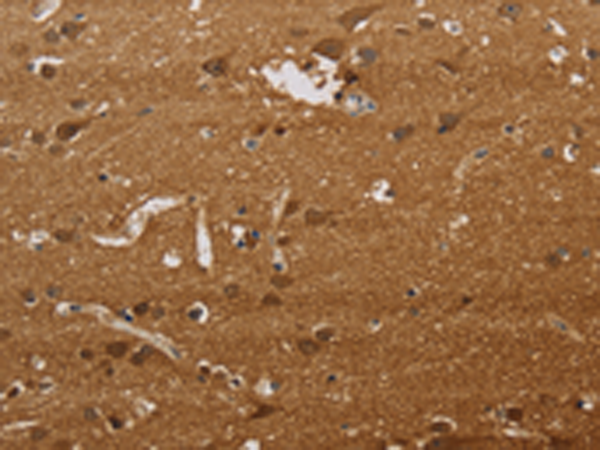

ELISA, IHC |

IHC positive control: |

Human brain and Human liver cancer |

IHC Recommend dilution: |

50-200 |